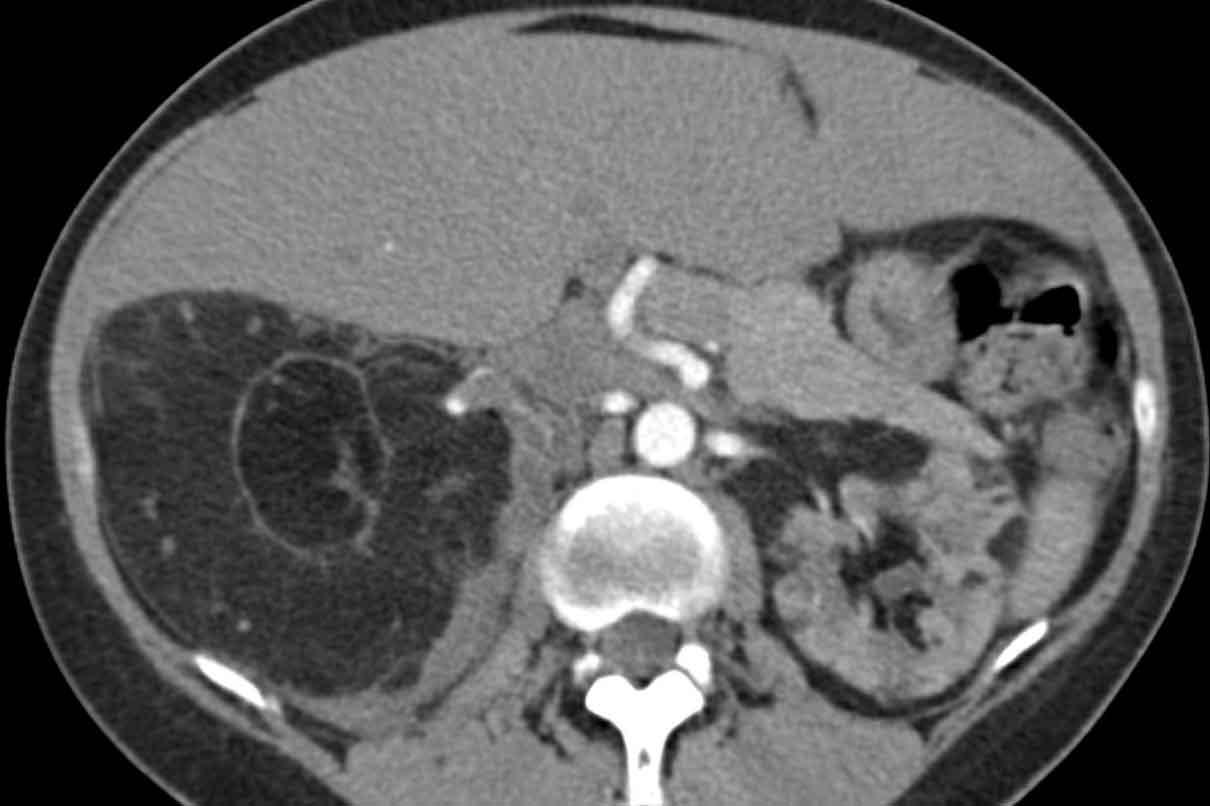

Ngoài ra, nhiều u cơ mỡ mạch máu (angiomyolipoma) được phát hiện ở vùng bụng trên.

Bệnh nhân này được xác định mắc LAM liên quan đến phức hợp xơ cứng củ (TSC – tuberous sclerosis complex).

Tỷ lệ hiện mắc u cơ mỡ mạch máu trong LAM tản phát là 40-50% và trong LAM liên quan TSC vào khoảng 80%.